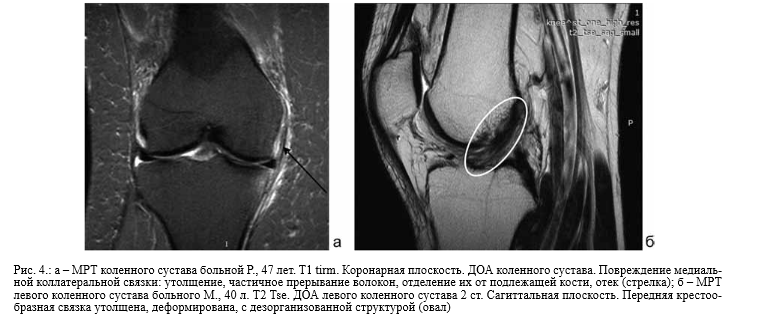

Синдром гоффа коленного 114 фото